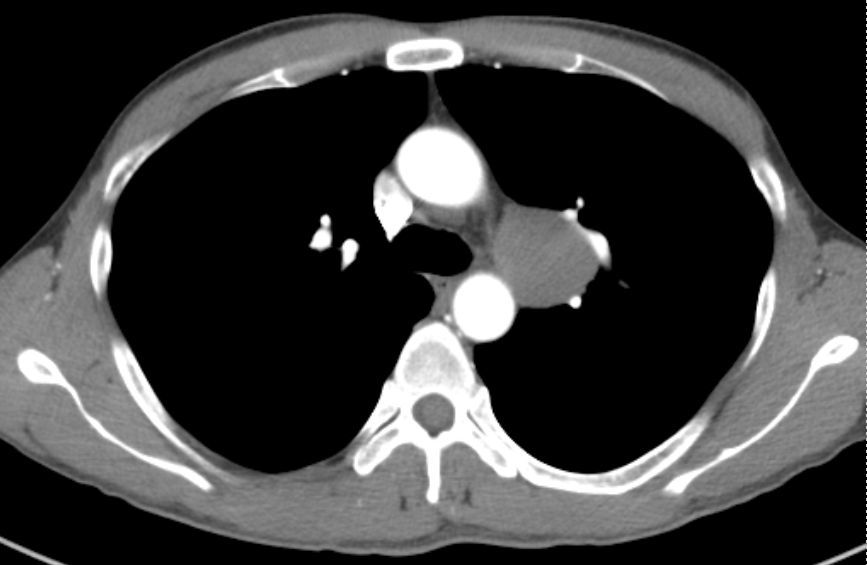

前纵隔结节前纵隔肿块胸腺囊肿thymiccyst和胸腺瘤如何区别需要手术吗